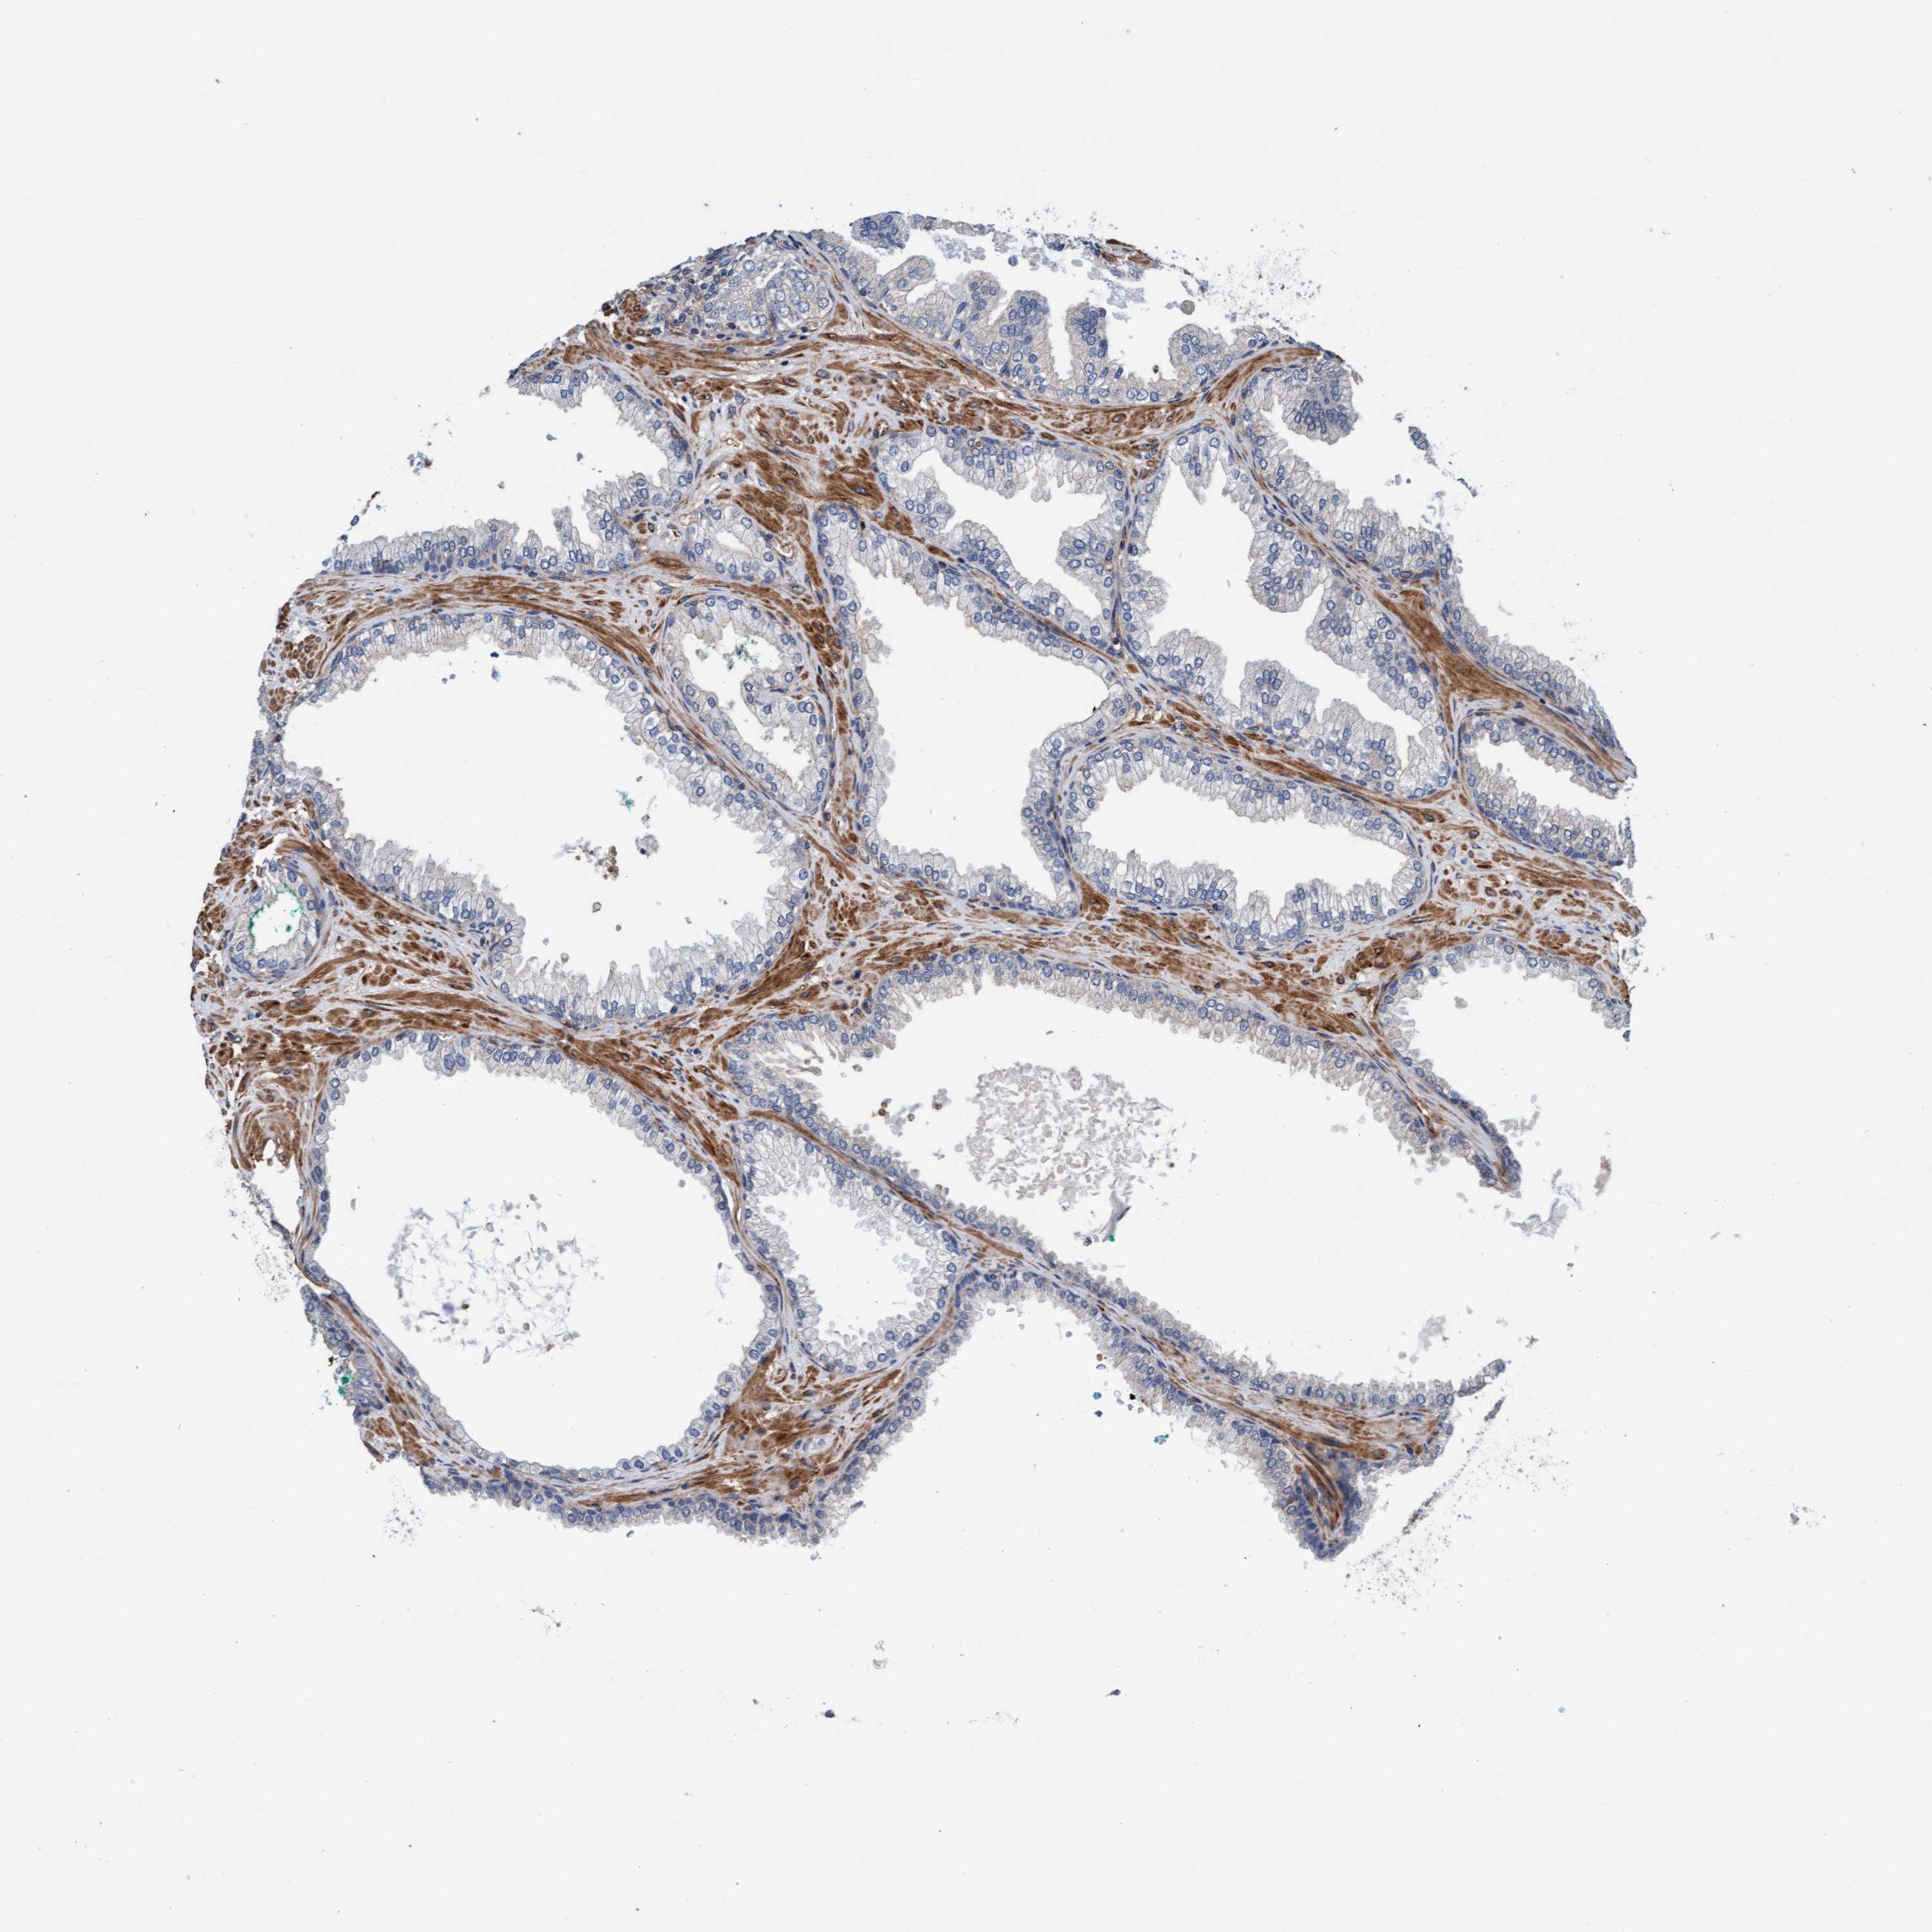

PROSTATE CANCER - Protein expressioni

A mouse-over function shows sample information and annotation data. Click on an image to view it in a full screen mode. Samples can be filtered based on level of antibody staining by selecting one or several of the following categories: high, medium, low and not detected. The assay and annotation is described here.

Antibody stainingi

Antibody staining in the annotated cell types in the current human tissue is reported as not detected, low, medium, or high, based on conventional immunohistochemistry profiling in selected tissues. This score is based on the combination of the staining intensity and fraction of stained cells.

Each image is clickable and will lead to virtual microscopy that enables deeper exploration of all samples and also displays staining intensity scores, fraction scores and subcellular localization as well as patient and tissue information for each sample.

Antibody HPA002552

Antibody HPA023201

Staining

High

Medium

Low

Not detected

Intensity

Strong

Moderate

Weak

Negative

Quantity

>75%

75%-25%

<25%

None

Location

Nuclear

Cytoplasmic/membranous

Cytoplasmic/membranous,nuclear

Adenocarcinoma, Low grade

Adenocarcinoma, Medium grade

Adenocarcinoma, High grade